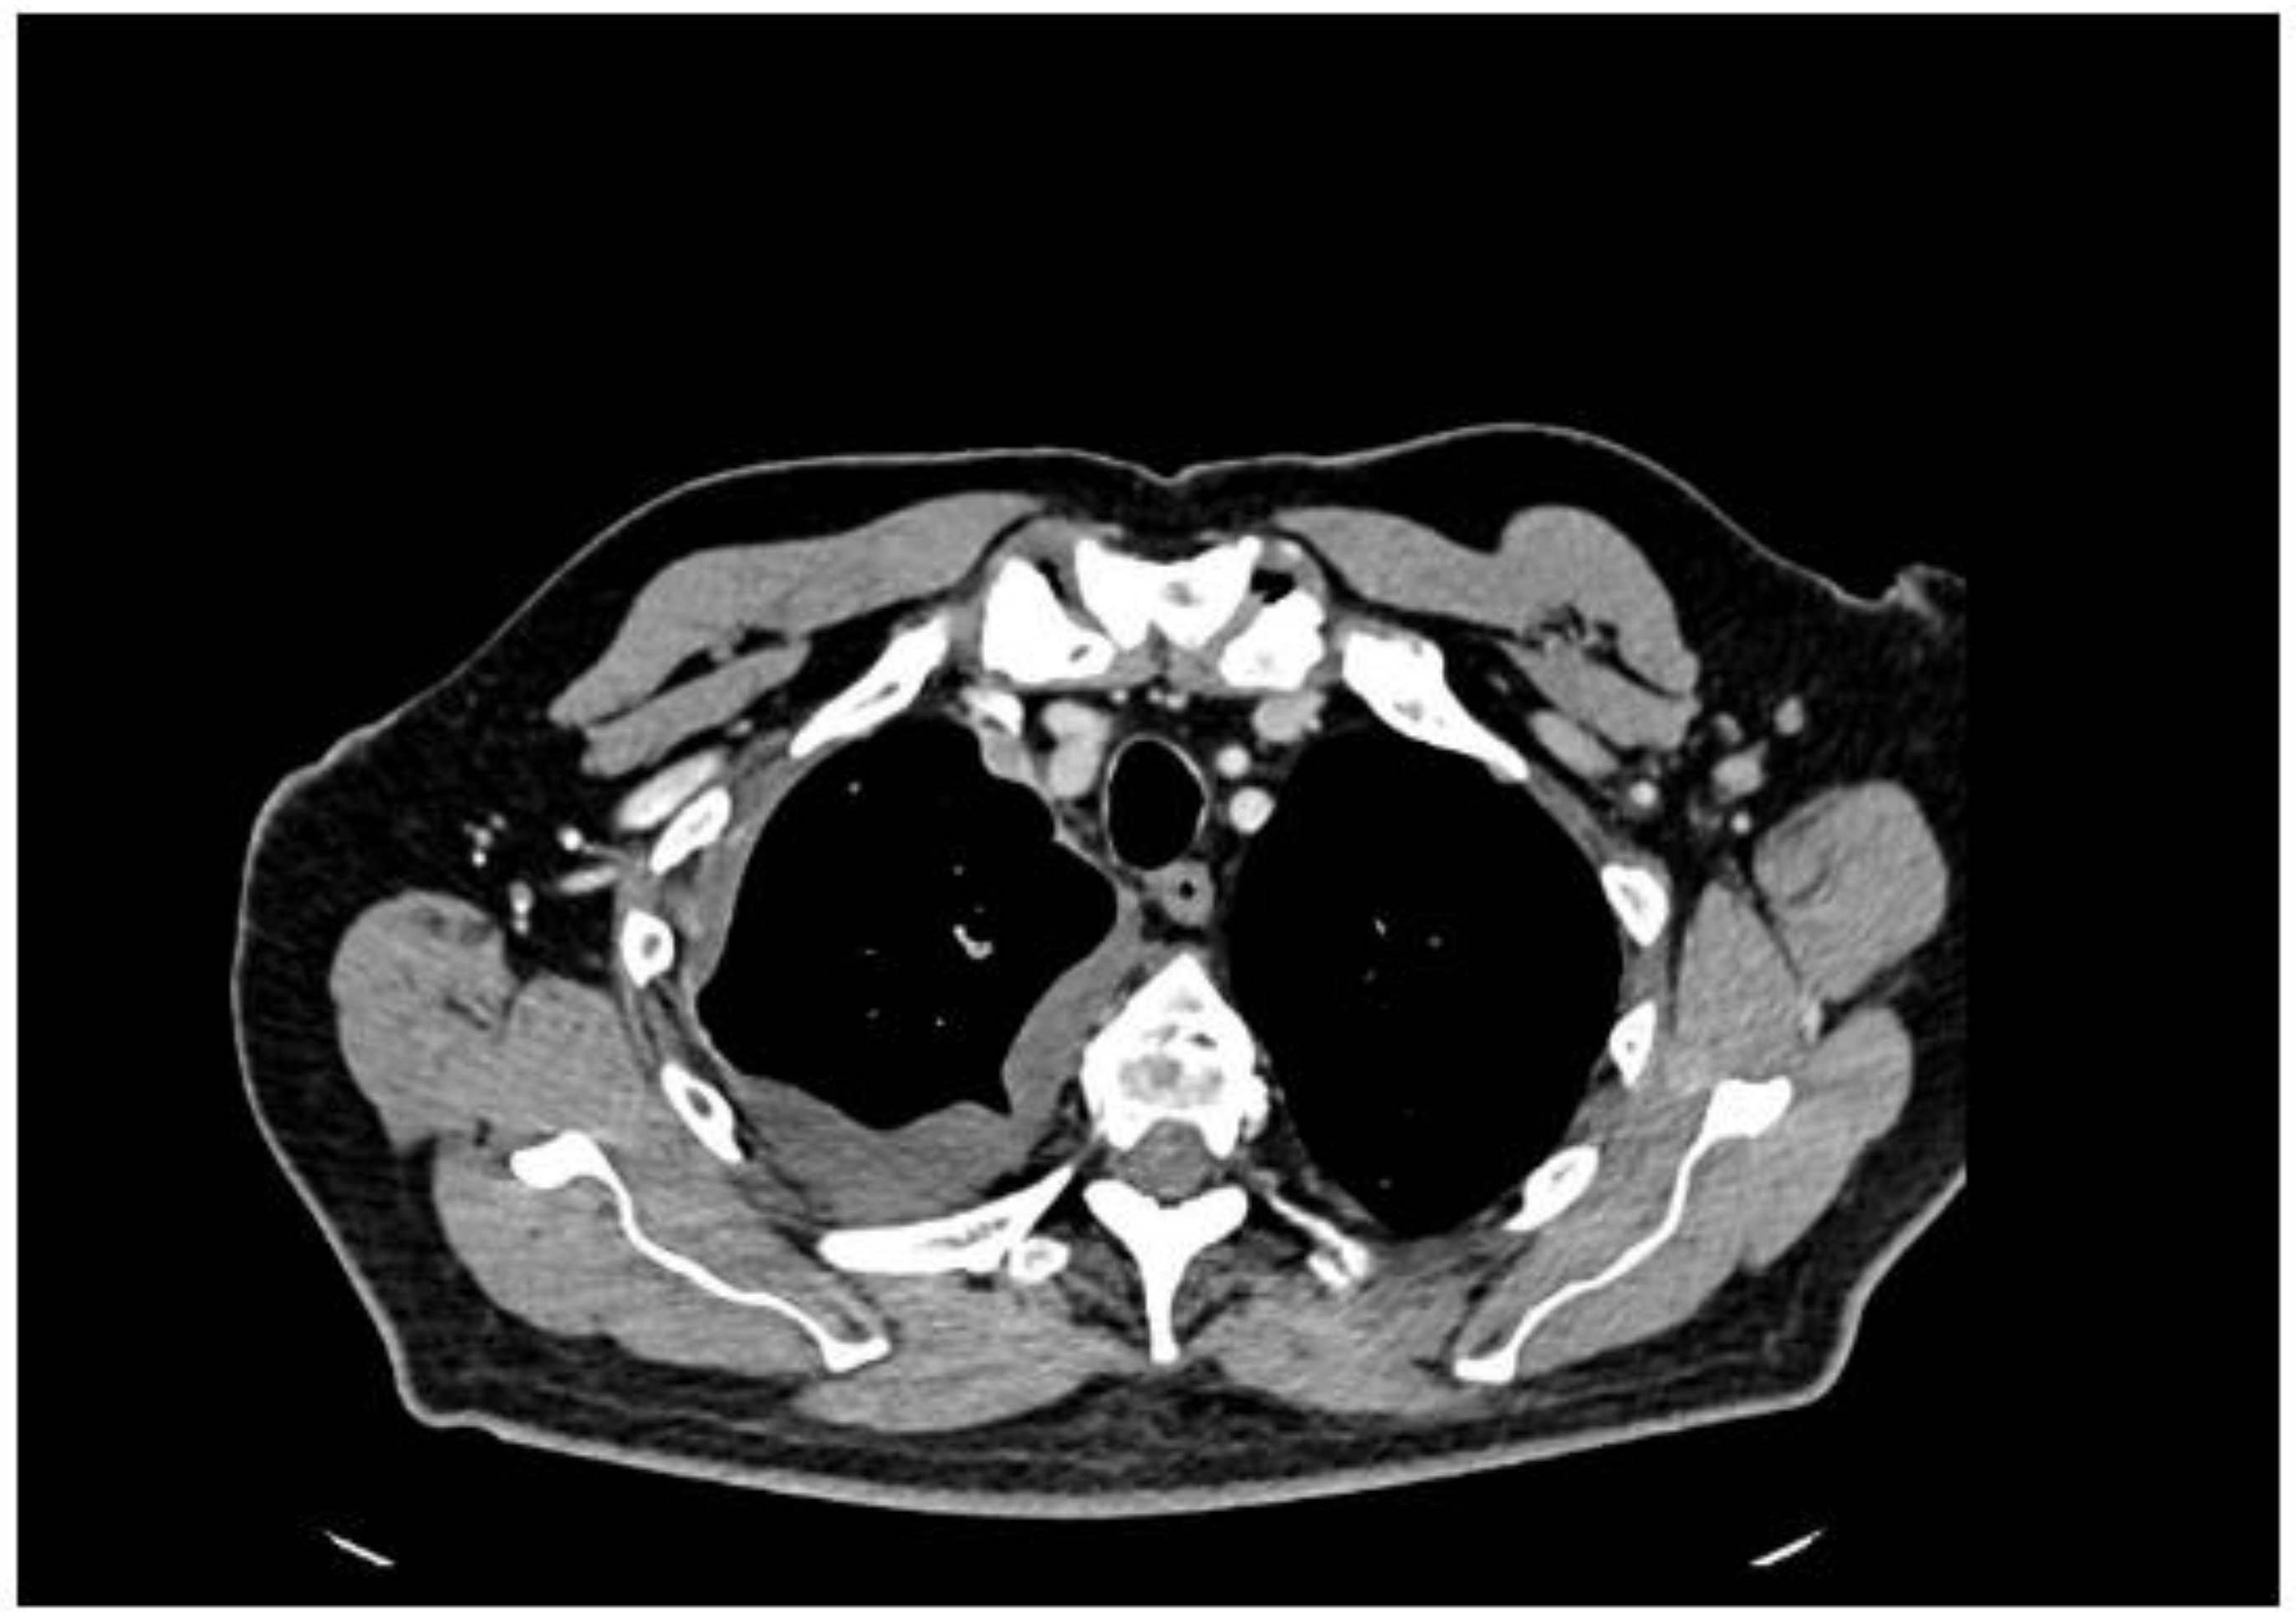

2. Case Presentation